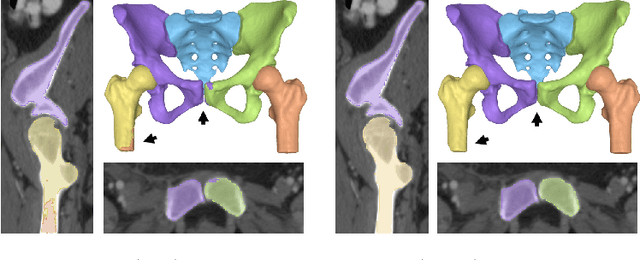

Abstract:Accurate geometry representation is essential in developing finite element models. Although generally good, deep-learning segmentation approaches with only few data have difficulties in accurately segmenting fine features, e.g., gaps and thin structures. Subsequently, segmented geometries need labor-intensive manual modifications to reach a quality where they can be used for simulation purposes. We propose a strategy that uses transfer learning to reuse datasets with poor segmentation combined with an interactive learning step where fine-tuning of the data results in anatomically accurate segmentations suitable for simulations. We use a modified MultiPlanar UNet that is pre-trained using inferior hip joint segmentation combined with a dedicated loss function to learn the gap regions and post-processing to correct tiny inaccuracies on symmetric classes due to rotational invariance. We demonstrate this robust yet conceptually simple approach applied with clinically validated results on publicly available computed tomography scans of hip joints. Code and resulting 3D models are available at: https://github.com/MICCAI2022-155/AuToSeg}